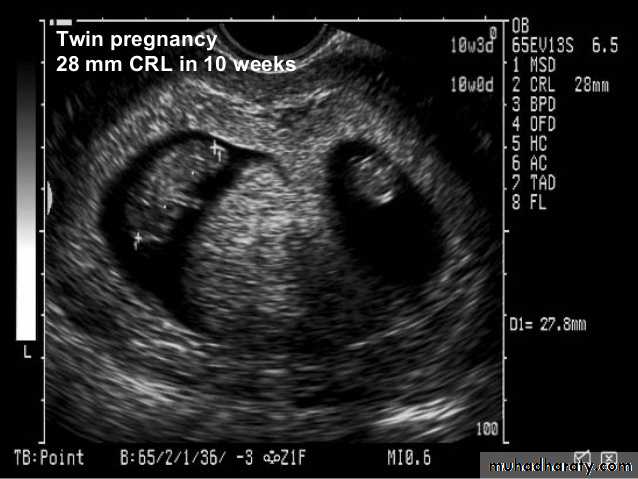

BPD together with head circumference (HC), abdominal circumference (AC), and femur length (FL) are computed to produce an estimate of fetal weight. In the second trimester this may be extrapolated to an estimate of gestational age and an estimated due date (EDD) .

The BPD should be measured on an axial plane that traverses the thalami, and cavum septum pellucidum. The transducer must be perpendicular to the central axis of the head, and thus the hemispheres and calvaria should appear symmetric.